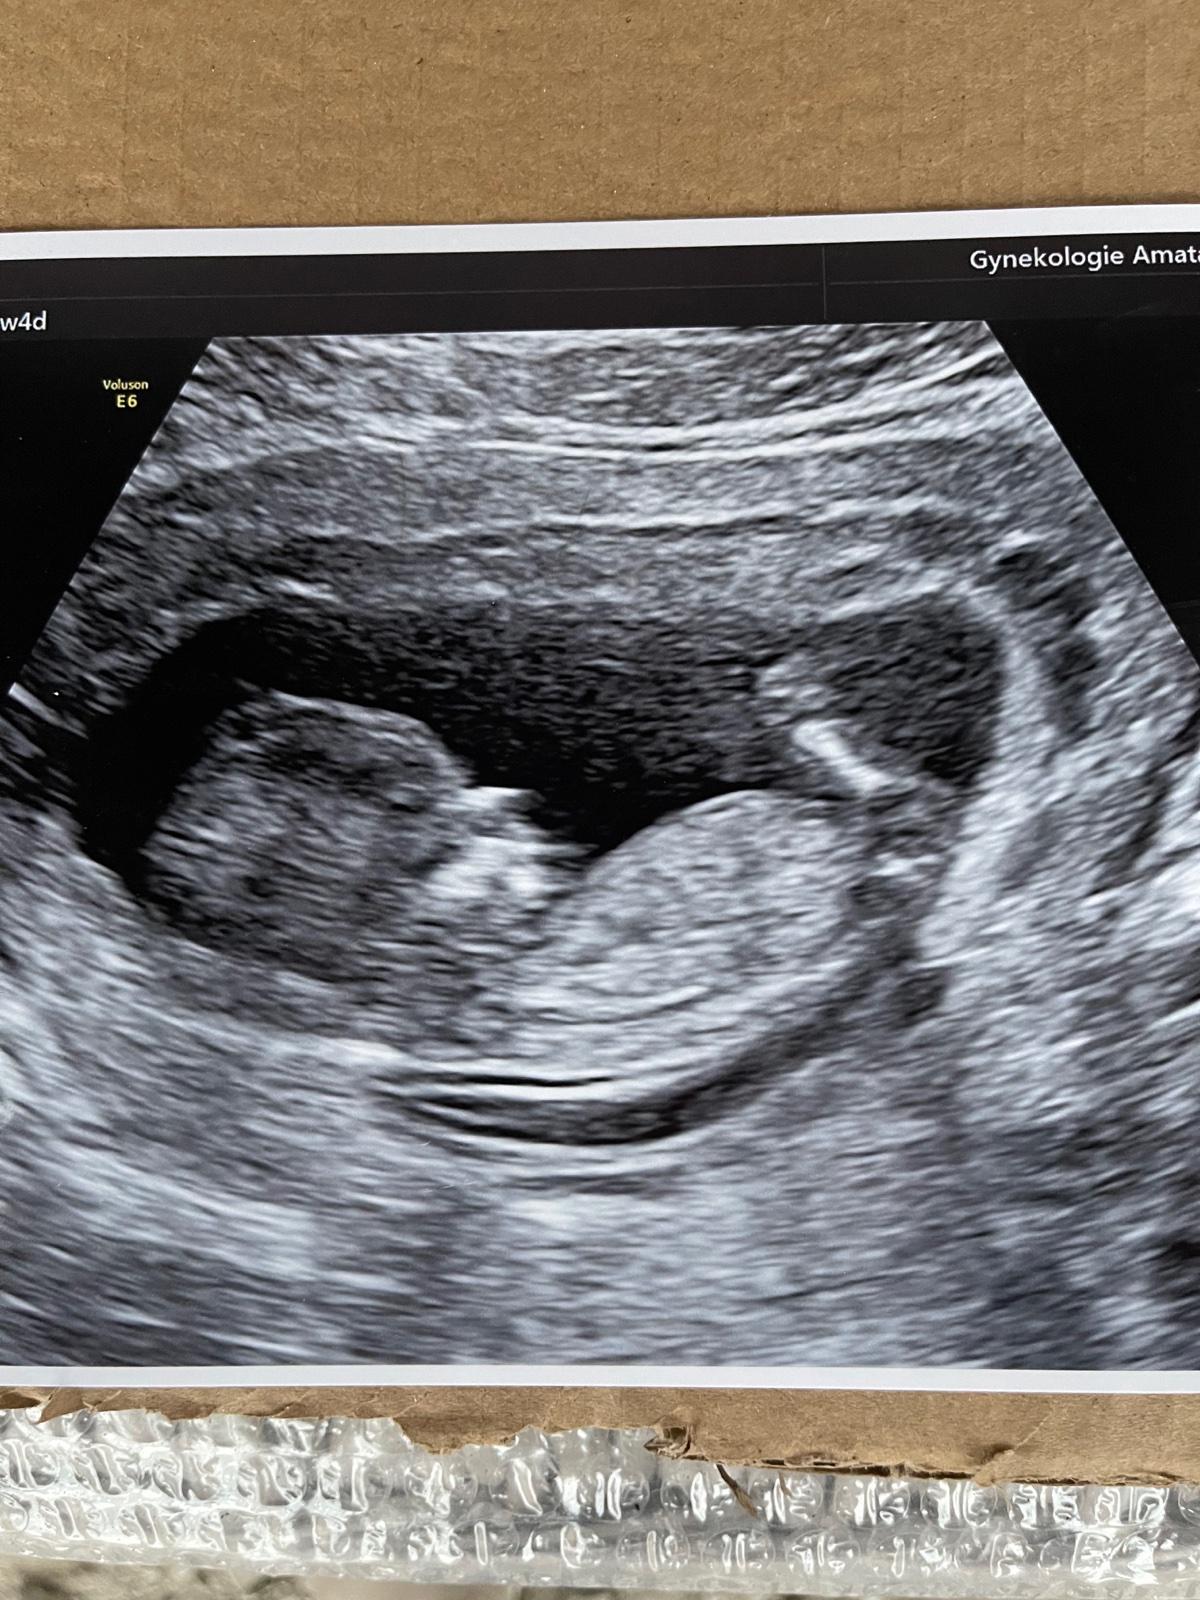

@siima12 jé, tak super 🥰 to je krásný 🥰 takže další holčička do party 😀😍

@adelaa1234 Jo přesně tak😁 říkám doktorovi to vypadá jako pindík 😁 a doktor no to, to není pindík, říkal že tohle mají všechny miminka 🤣 nevím co to teda bylo

@siima12 Jojo mají, ale taky nevím jak se to jmenuje 😅😊 tak hlavně , že je vše v pořádku 😊